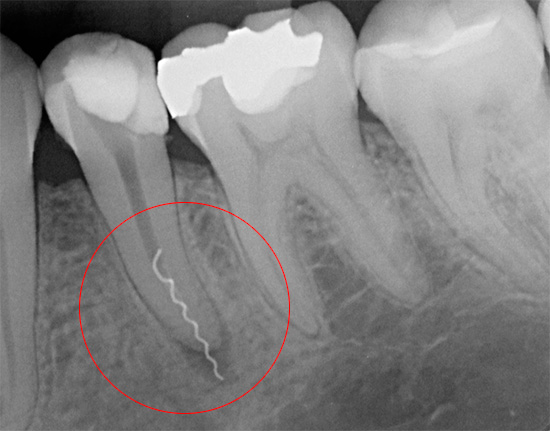

La foto sotto mostra un esempio di uno strumento dentale rotto in un canale:

Tuttavia, se rompere lo strumento può essere definito un classico errore del medico, a volte è difficile prevedere il sanguinamento dal canale, ad esempio il distacco della polpa durante l'estrazione della polpa può essere troppo profondo. Ecco perché un certo numero di dentisti non ritiene opportuno rischiare rimuovendo il nervo dal dente con un estrattore di polpa e preferisce un altro metodo: tagliare gradualmente i tessuti molli con file con abbondante risciacquo graduale del canale con antisettici.

L'estrattore di polpa nel canale viene interrotto a causa di una violazione della tecnica di lavoro con esso (torsione eccessiva nel canale) o quando si utilizzano strumenti non idonei (difettosi).

Se il sanguinamento dal canale dentale si interrompe più spesso rapidamente e non ha conseguenze gravi, l'estrazione del pezzo sinistro dell'estrattore di polpa è una procedura complessa che richiede le competenze appropriate e determinate attrezzature dal medico. Lasciare il residuo “sporco” dell'estrattore di polpa nel canale non trattato significa rimuovere il dente - e questa è solo una questione di tempo.